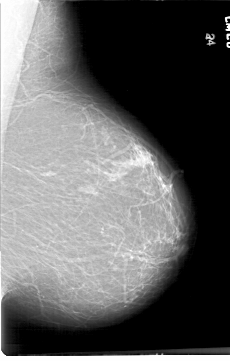

D_4196_1.RIGHT_CC

RIGHT_CC LINES 6331 PIXELS_PER_LINE 4096 BITS_PER_PIXEL 12 RESOLUTION 43.5 OVERLAY

FILE: D_4196_1.RIGHT_CC.OVERLAY

TOTAL_ABNORMALITIES 1

ABNORMALITY 1

LESION_TYPE CALCIFICATION TYPE PLEOMORPHIC DISTRIBUTION CLUSTERED

ASSESSMENT 0

SUBTLETY 5

PATHOLOGY BENIGN

TOTAL_OUTLINES 1

BOUNDARY